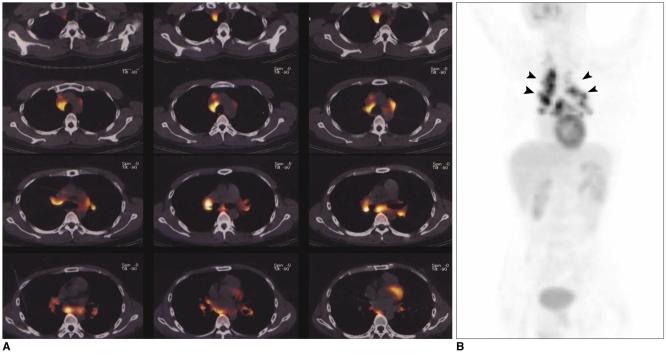

Fluorodeoxyglucose (FDG)-positron emission tomography (PET) is being used more and more to differentiate benign from malignant focal lesions and it has been shown to be more efficacious than conventional chest computed tomography (CT). However, FDG is not a cancer-specific agent, and false positive findings in benign diseases have been reported. Infectious diseases (mycobacterial, fungal, bacterial infection), sarcoidosis, radiation pneumonitis and post-operative surgical conditions have shown intense uptake on PET scan. On the other hand, tumors with low glycolytic activity such as adenomas, bronchioloalveolar carcinomas, carcinoid tumors, low grade lymphomas and small sized tumors have revealed false negative findings on PET scan. Furthermore, in diseases located near the physiologic uptake sites (heart, bladder, kidney, and liver), FDG-PET should be complemented with other imaging modalities to confirm results and to minimize false negative findings. Familiarity with these false positive and negative findings will help radiologists interpret PET scans more accurately and also will help to determine the significance of the findings. In this review, we illustrate false positive and negative findings of PET scan in a variety of diseases.